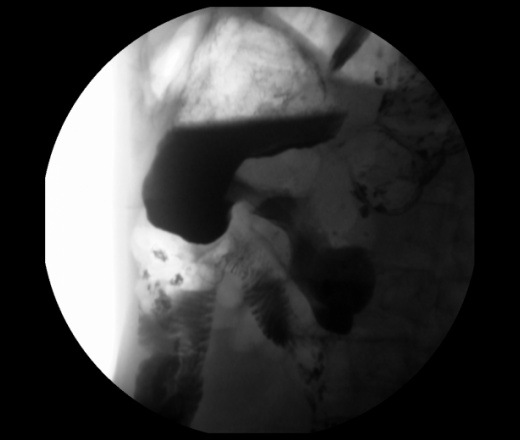

Мужчина 73 года. Жалобы на сниженный аппетит, слабость. Исследование выполенено через несколько дней после ирригоскопии. По результатам ЭФГДС гастрит.

Угол желудка развернут, ригиден. Стойкое циркулярное сужение антрального отдела.Перистальтики нет. Складки прослеживаются.

Эндофитный C-r антрального отдела.